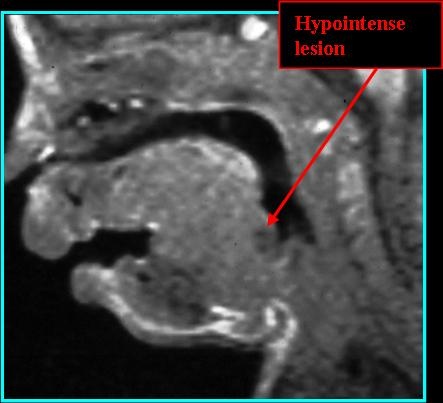

- On MR: can be hypo- or hyperintense on T1 depending on protein content; hyperintense on T2; rim-enhancing on T1 post-contrast if infected